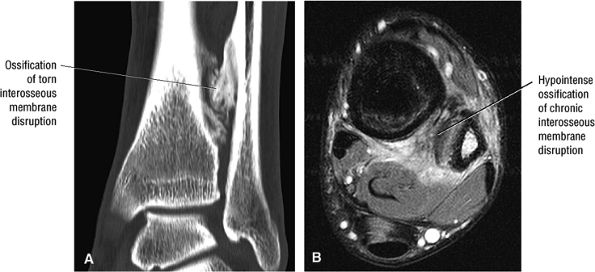

The syndesmotic ligaments consist of the anterior syndesmotic or anterior inferior tibiofibular ligament and the posterior syndesmotic or posterior inferior tibiofibular ligament, the interosseous membrane, and the transverse tibiofibular ligament.